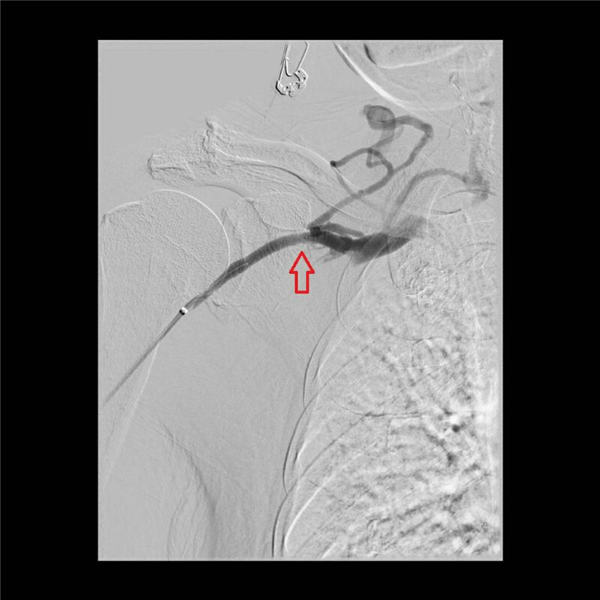

随后,两位主任通力协作,通过放置球囊扩张的方法,对血管的三处狭窄段分别用球囊扩张后,可见狭窄段部分或者完全扩张(下图红色箭头所示)。

最后,再次造影,发现三处血管狭窄基本消失,血液顺畅回流到上腔静脉(如下图)。